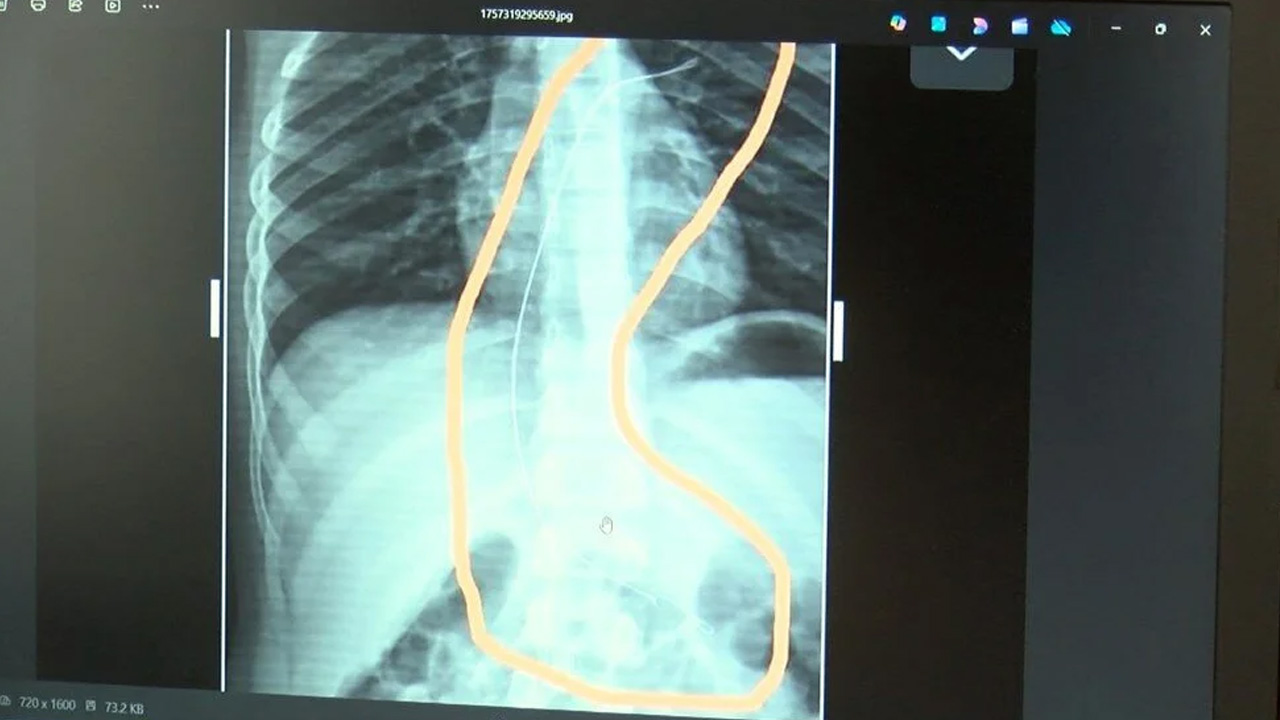

Burada çekilen röntgen ve MR'da Aram'ın vücudunda kateter unutulduğu görüldü.

Diyarbakır'daki Gazi Yaşargil Eğitim ve Araştırma Hastanesi Kadın Doğum ve Çocuk Ek Binası'na sevk edilen Aram, 5,5 saat süren riskli bir ameliyata alınarak 18 santimetre uzunluğundaki kateter çıkarıldı.

Gece saatlerinde çocuklarını hastaneye götürdüklerini anlatan anne, "Doktor röntgeni gösterdi. Tel kalmıştı. Çok kötü bir şekilde. Acil doktoru film çektikten sonra bize bir tel parçasını gösterdi. Bizi bekletmeden Diyarbakır’a sevkimizi verdiler." dedi.